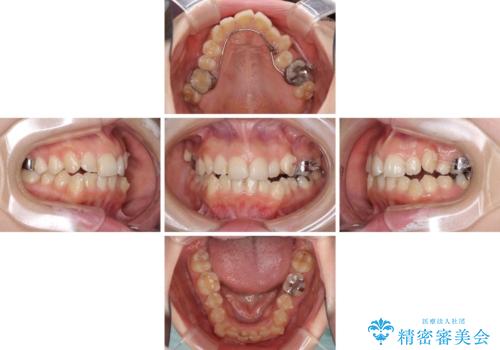

顕著な八重歯をインビザラインで治せるところまで改善

補助装置だけでなく、部分的にワイヤー矯正も使用しましたが、上下のスペースは改善しきれず、側切歯(前から2番目の歯)や顕著な八重歯は、インビザラインで治療するには限界があることがよく分かりました。

より良い仕上がりを希望される場合には、ワイヤー装置による矯正治療がお勧めとなります。